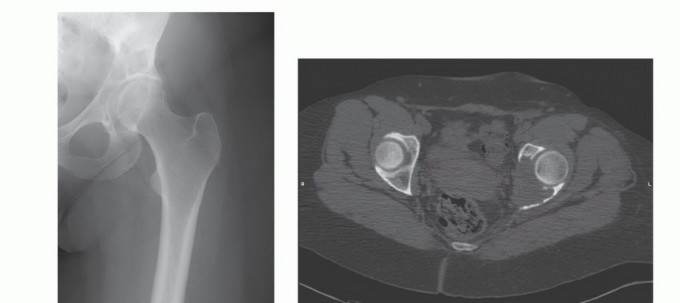

- الأشعة السينية (X-rays): هي الفحص الأولي، ويمكن أن تكشف عن التغيرات العظمية مثل التآكل أو التصلب أو الكسور.

- التصوير المقطعي المحوسب (CT Scan): يوفر صورًا مقطعية مفصلة للعظام والأنسجة الرخوة، ويساعد في تحديد حجم الورم، مدى انتشاره داخل العظم، وعلاقته بالهياكل المحيطة.

- التصوير بالرنين المغناطيسي (MRI): يُعد الأداة الأكثر حساسية لتقييم الأنسجة الرخوة ونخاع العظم، ويكشف عن النقائل في مراحلها المبكرة، ويحدد مدى انتشار الورم في القناة الشوكية أو الأعصاب.